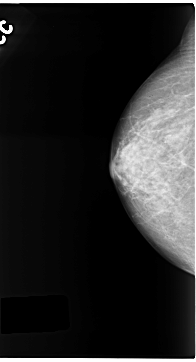

C_0141_1.RIGHT_MLO

RIGHT_CC LINES 4704 PIXELS_PER_LINE 2544 BITS_PER_PIXEL 12 RESOLUTION 50 NON_OVERLAY

RIGHT_MLO LINES 4704 PIXELS_PER_LINE 2440 BITS_PER_PIXEL 12 RESOLUTION 50 NON_OVERLAY